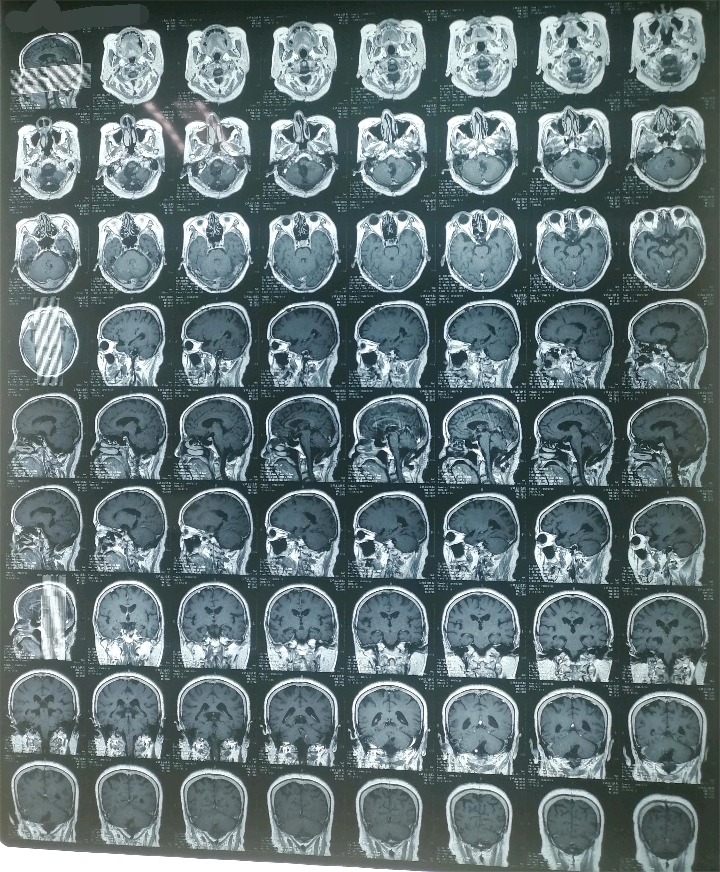

术前资料

术后资料